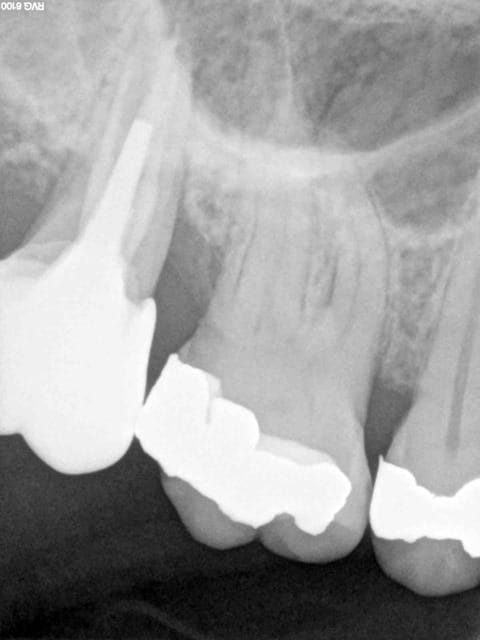

Patiente se présentant avec une fracture cuspide disto-vestibulaire de 16.

Dent ne pouvant etre reconstituée de facon durable par un matériau inséré en phase plastique ( composite, amalgame).

J'ai suivit ton aventure cerec chicot, ce qui me surprend c'est la facilité avec laquelle tu dévitalises une dent pour une question de remboursement, en terme de durée de vie sur l’arcade une dent dévitalisée n'a plus le même capital qu'une dent vivante.